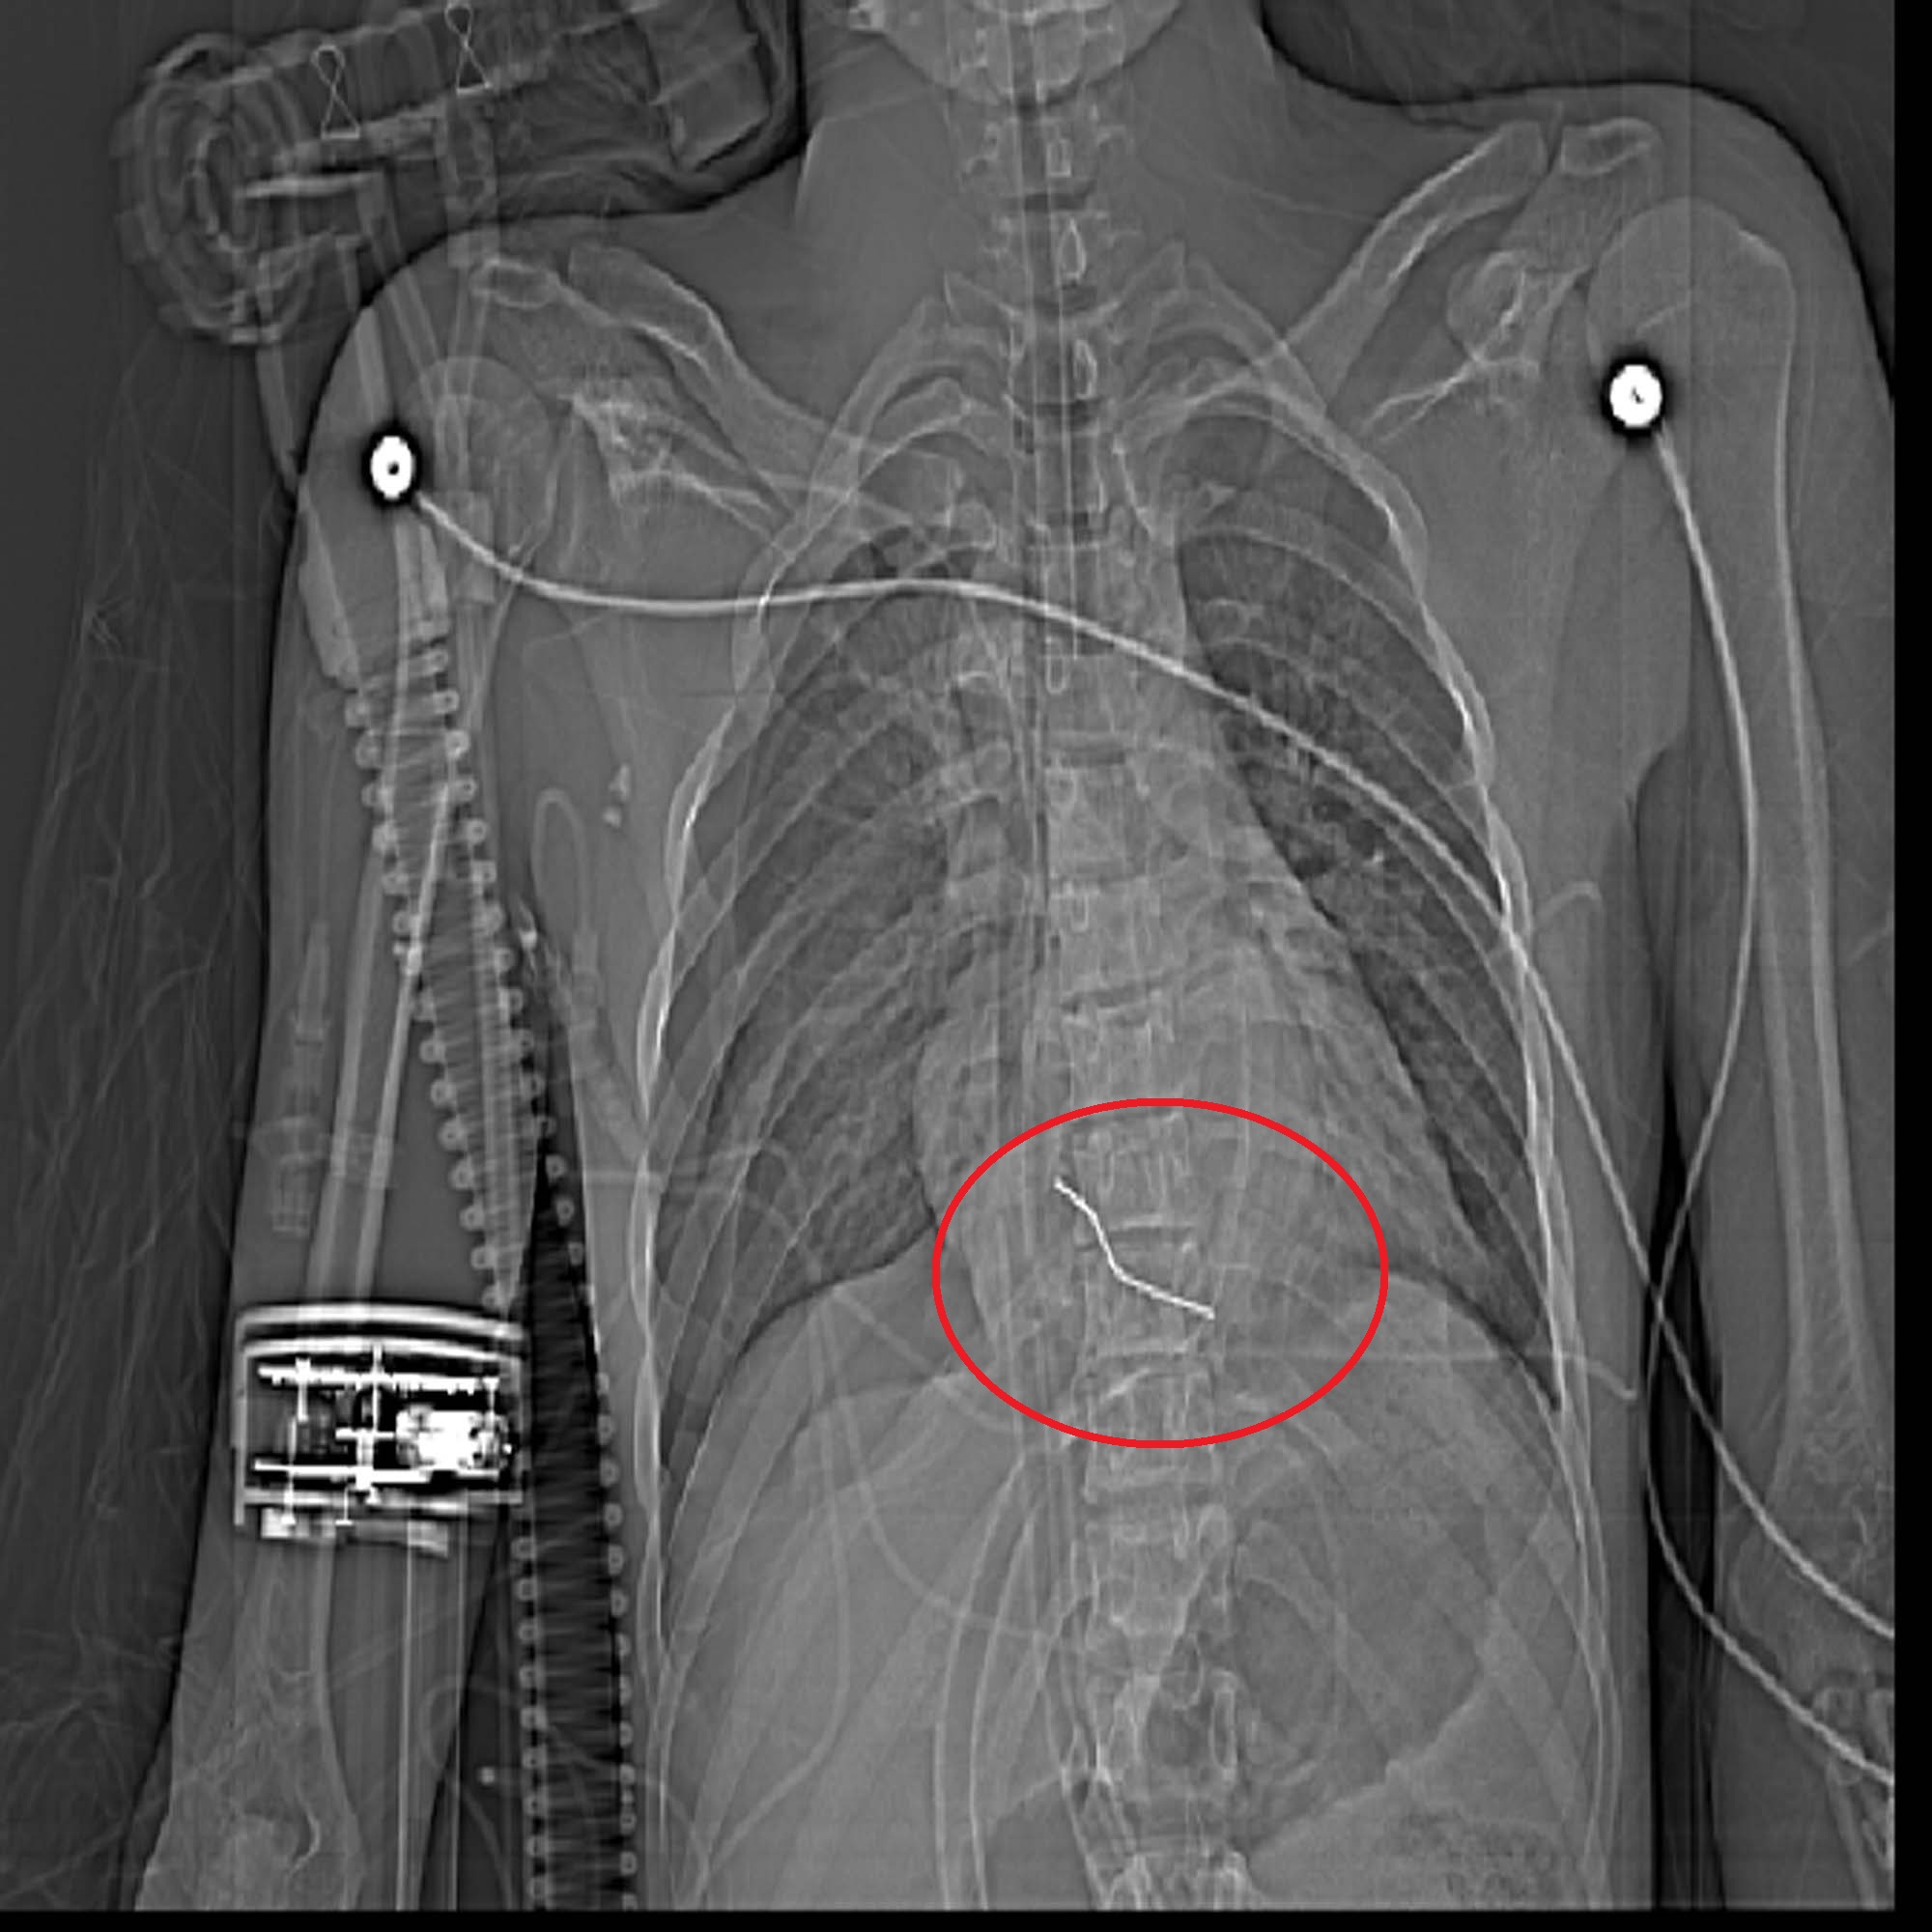

خارج کردن میخ 5 سانتیمتری از قلب پسرجوان سبزواری

روابط عمومی بیمارستان تخصصی و فوق تخصصی حشمتیه از نجات جان بیمار بعد از خارج کردن میخ 5 سانتیمتری از قلب بیمار خبر داد.

به گزارش روابط عمومی بیمارستان حشمتیه دکتر راستی ریاست بیمارستان حشمتیه عنوان کرد: 23 خرداد ماه ، ساعت 22:00 جوان 21 ساله به دلیل فرو رفتن میخ به ناحیه قفسه سینه و قلب وی از شهر داورزن به بیمارستان حشمتیه منتقل شد. وی افزود: بیمار در هنگام ورود به بیمارستان دچار کاهش هوشیاری و افت شدید علایم حیاتی بوده است و در حالت احیای قلبی و ریوی سریعا به بخش اتاق عمل منتقل می گردد و تحت عمل جراحی قرار می گیرد. خوشبختانه تیم جراحی قلب این بیمارستان به سرپرستی دکترعبدالرحمن جراح قلب همچنین متخصص بیهوشی قلب دکتر یوسفی ، پزشک متخصص داخلی قلب دکتر اسماعیلیان وتیم اتاق عمل قلب در یک عمل جراحی 1.5 ساعته اقدام به بازکردن قفسه سینه و خارج کردن میخ از قلب این بیمار می نمایند.. دکتر عبدالرحمن با بیان این نکته که با توجه به شرایط بیمار نیاز فوری به انجام عمل جراحی بوده است گفت میخ 5 سانتیمتری از سمت چپ استخوان جناغ بیمار وارد و به بطن راست قلب آسیب وارد کرده بود.بعد از باز شدن قفسه سینه ،بعلت عدم حرکت قلب با انجام ماساژ باز قلب تا ضربان قلب برگردد. بعد ازترمیم ناحیه پارگی و خارج کردن میخ قفسه سینه بیمار بسته شد و بیمار به بخش مارقبت های ویژه قلب باز منتقل گردید.. دکتر راستی در ادامه گفت که بیمار با هوشیاری کامل و وضعیت عمومی بسیار مطلوب بعد از پنج روز تحت مراقبت بودن 28 خرداد مرخص گردید. وی در ادامه از زحمات تیم جراحی و تیم پرستاری بخش مراقبت های ویژه قلب باز تشکر کرد که با عملکرد مطلوب خود باعث بهبود حال بیمار شدند.